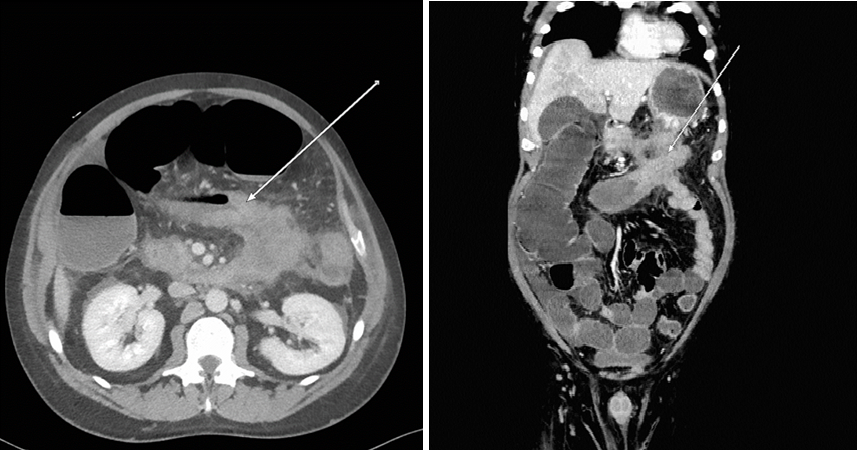

Mechanical Colonic Obstruction as A Complication of Necrotizing Pancreatitis: A Case Report and Literature Review

Dr. Shahad Al-Ghamdi, Dr. Ayed Al-Mutairi

International Journal of Innovative Research in Medical Science·August 10, 2022